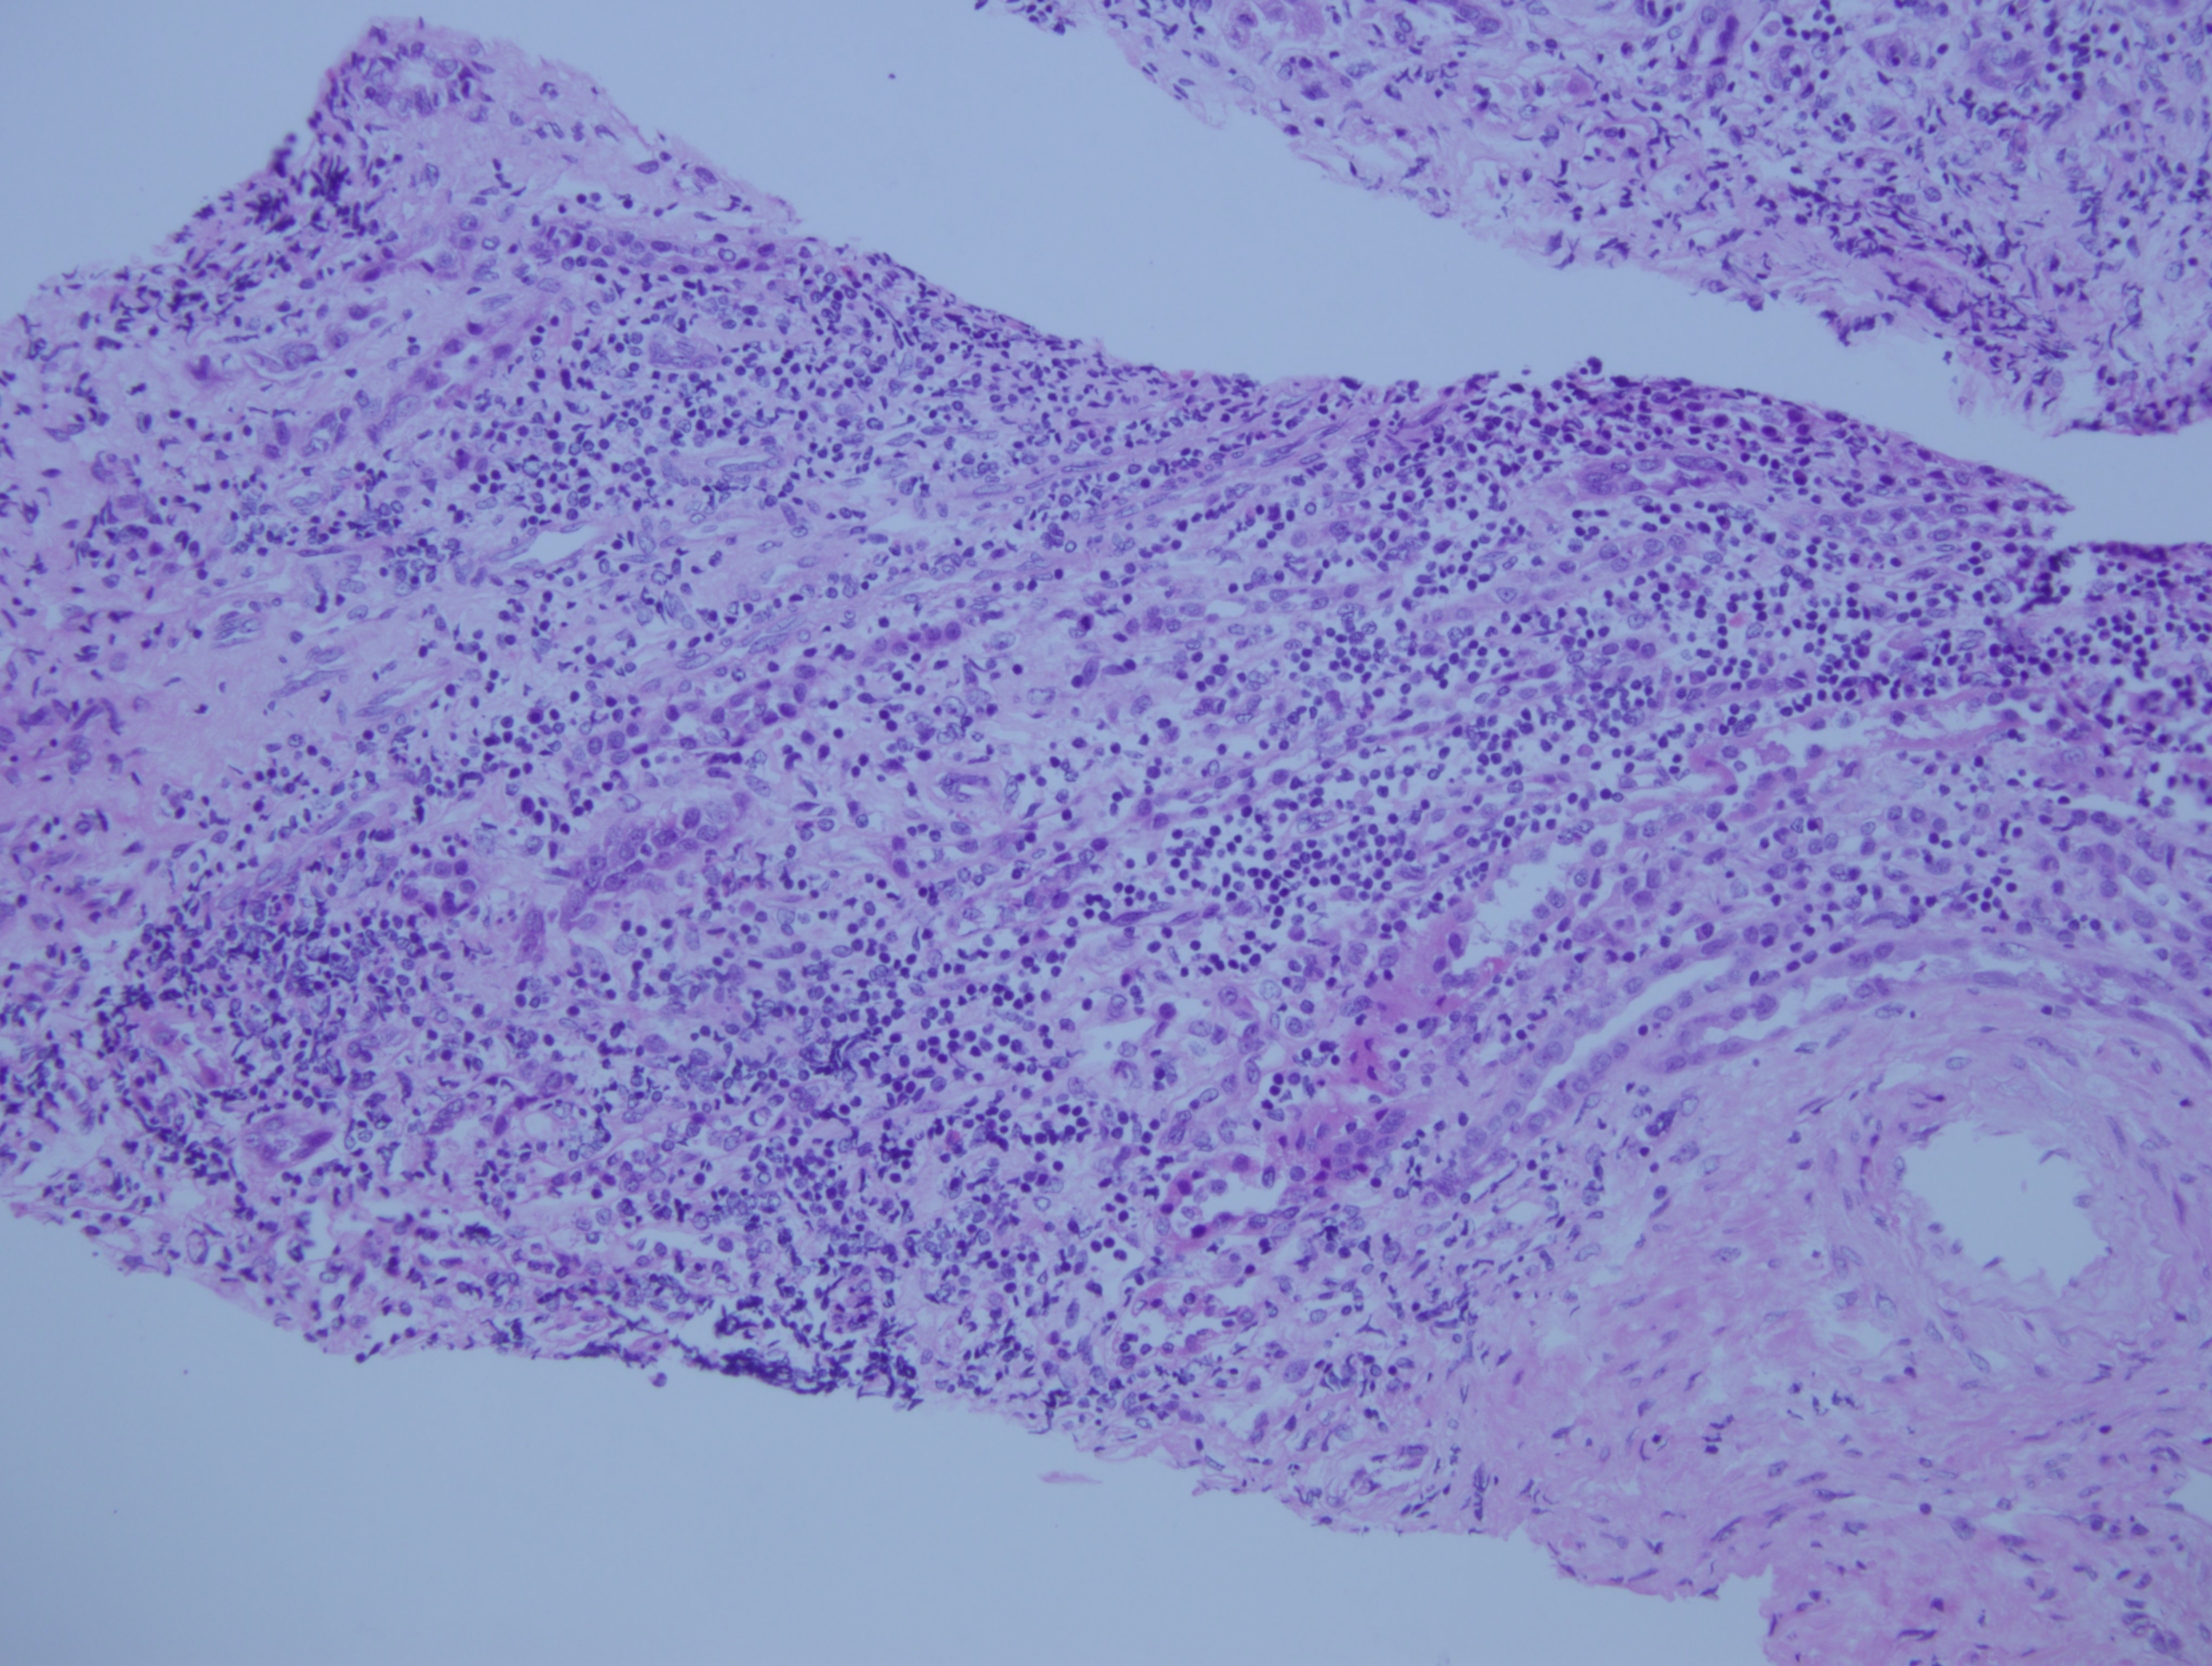

Biopsia renal, hematoxilina eosina

Nefritis tubulo intersticial por leflunomide